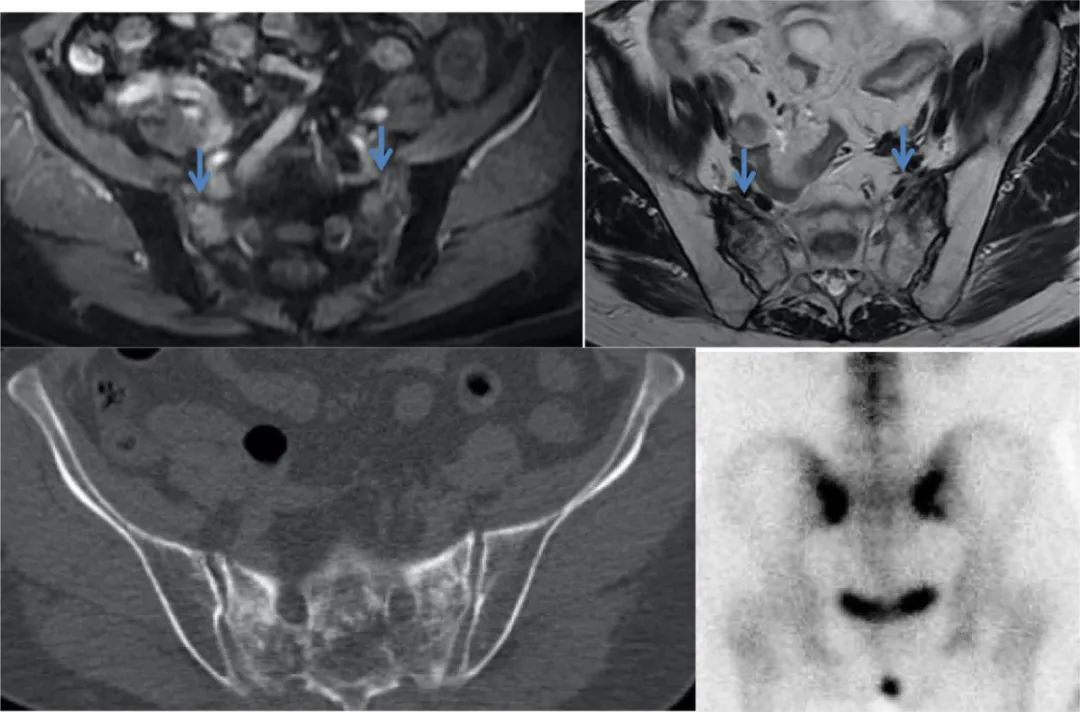

图 1 Case1. T1WI 和 T2WI 显示骶骨左侧份异常信号(蓝色直箭头)、增强扫描明显强化(蓝色弯箭头),T1 压脂高信号(红色直箭头)。

图 2 Case1. Tc-99m MDP 全身骨显像及 SPECT/CT 显像显示骶骨机能不全骨折呈特征性「H」 征。蓝色箭头清晰显示 CT 图像上的骶骨骨折线。

CASE 2

图 3 Case 2. MR T1WI 及增强扫描显示双侧骶骨异常信号伴强化(蓝色直箭头);全身骨显像显示骶骨骨折呈特征性「H」征,CT 示骶骨骨折处骨质不均匀增高、硬化。